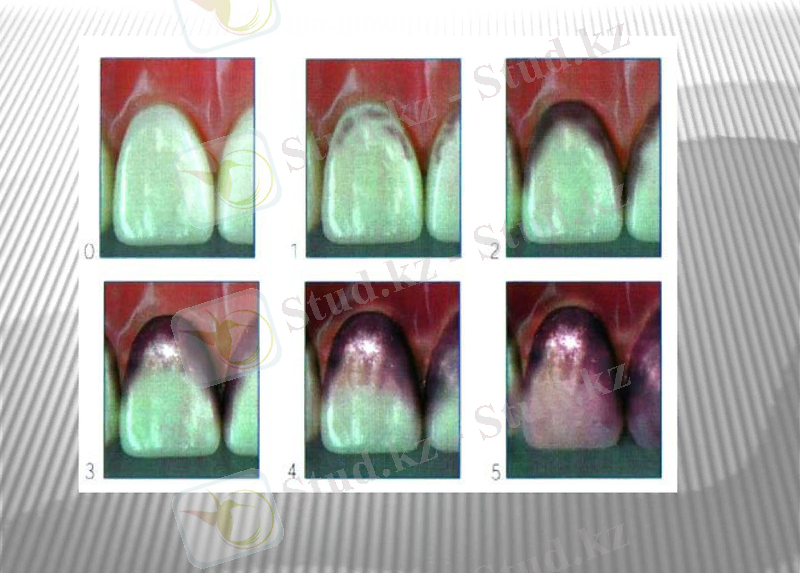

Нави индексі(1962) (I. M. Navy, E. Quiglty, I. Hein) .

Ауыз қуысы тіндерінің, алдыңғы тістердің еріндік беткейлерінің боялу индекстерін санайды. Зерттеу алдында ауыз қуысын 0, 75 % функсин ерітіндісімен шаяды.

Индекс саны

Мәні

0

Тіс қағы жоқ

1

Тіс қағы сирек кездеседі.

2

Қызылиек маңында тіс қағы(бляшка) кездеседі.

3

Тіс сауытының 3/1 бөлігі боялған.

4

Тіс сауытының 3/2 бөлігі боялған.

5

Тістің барлық бөлігі боялған.